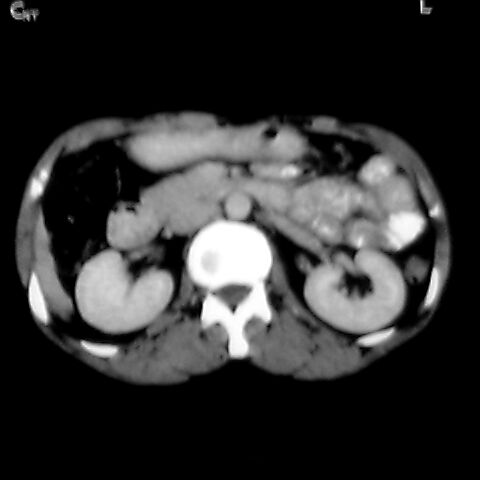

女 48岁 食道癌术前体检发现脾占位。

脾胀内部巨大低密度肿块,边界清或不清,中心坏死,轻度增强,内见散在钙化,结合食道癌病史多考虑:转移癌.

脾脏低密度灶伴钙化,增强化明显,中心见液化坏死灶,强化延时明显。考虑血管瘤。转移瘤待排。

考虑脾脏血管瘤,中央低密度为血栓形成